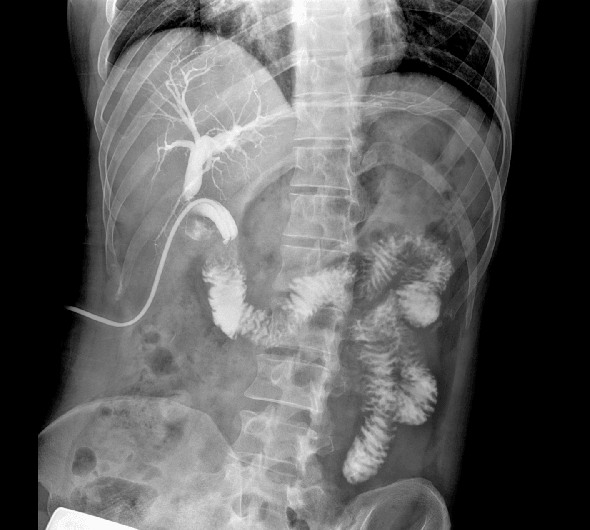

临床图像

创新动态断层多功能胃肠 DR 系列